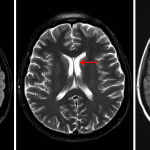

- Enlarged intraorbital left optic nerve with T2/STIR hyperintensity, restricted diffusion, and marked enhancement

- No evidence of acute intracranial infarct, hemorrhage, mass effect, or hydrocephalus

- No significant white matter disease

- Optic neuritis

Findings consistent with left optic neuritis.